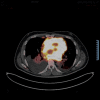

This case highlights the role of cardiac imaging in detecting the evolution of cardiac involvement during thoracic lymphoma and the importance of optimal chemotherapy, which leads to a rapid improvement of the cardiac dysfunction, without the need for cardiac pharmacotherapy.

Keywords: cardiac dysfunction; cardiac mass infiltration; echocardiogram; secondary cardiac lymphoma.